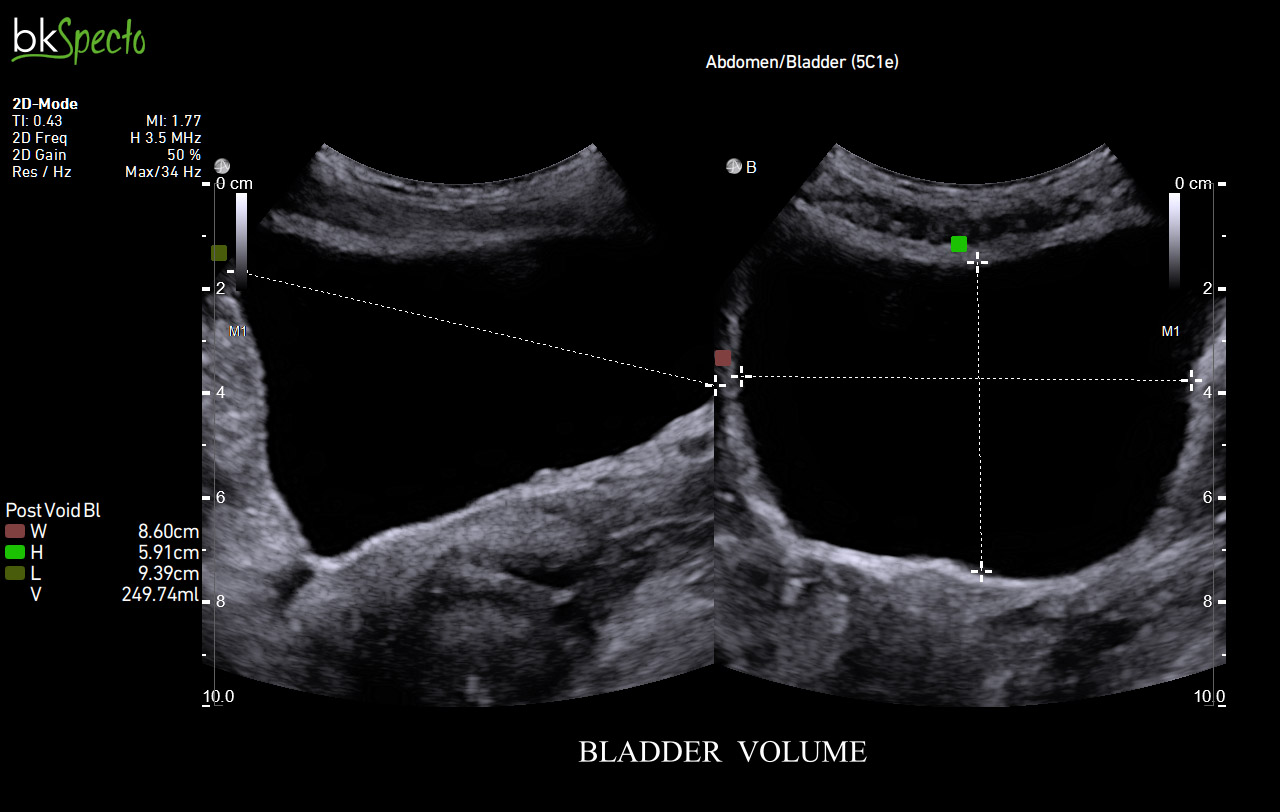

BkSpecto là hệ thống siêu âm chuyên về các thủ thuật can thiệp cho các chuyên khoa: Tiết niệu, gây mê, cơ, tuyến vú, tuyến giáp, sản phụ khoa và hậu môn trực tràng.

- Là thương hiệu đầu tiên và hàng đầu thế giới với hơn 40 năm chuyên về sinh thiết và dẫn hướng điều trị qua hình ảnh siêu âm. BkSpecto được thiết kế đặc biệt cho các ký thuật: Sinh thiết u xơ tiề liệt tuyến, sinh thiết qua đồng bộ hình ảnh siêu âm và MRI, điều trị u bằng đặt hạt phóng xạ, thăm khám dương vật/tinh hoàn, thăm khám thận/bàng quang, tán sỏi thận qua da PCNL.